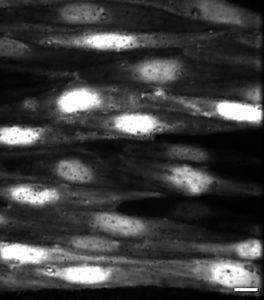

This picture shows what the cells look like on the inside of the blood vessels when I look at them with our powerful microscope. These cells are called ‘endothelial cells‘. I am interested in these cells because they tell the artery to open and let more blood through, but when people become fat these cells don’t seem to work properly.